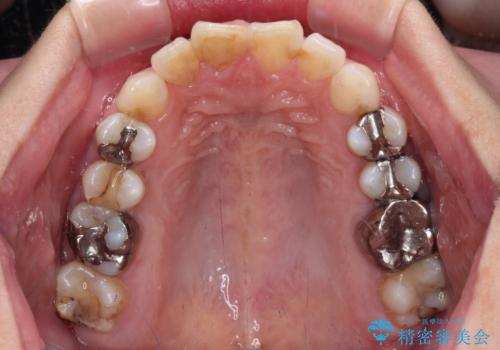

- 前歯のデコボコを治したいとのことで来院された患者様です。

上下顎ともに歯列全体の後方移動とIPR(歯と歯の間を削る)によってデコボコが解消するように設計し、インビザラインにより治療を行うこととしました。

しっかりと装着時間を守ってくださったのですが、途中妊娠にともなう悪阻や出産といったイベントがあり、予定よりも治療期間が長くなりました。